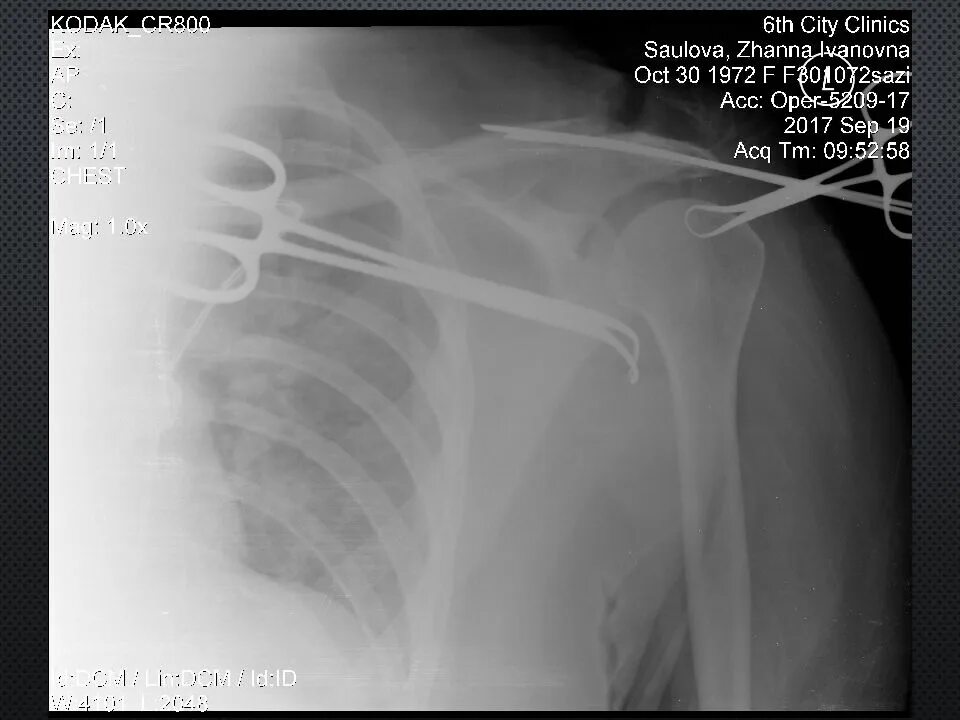

Дегенеративные изменения акромиально ключичного сочленения